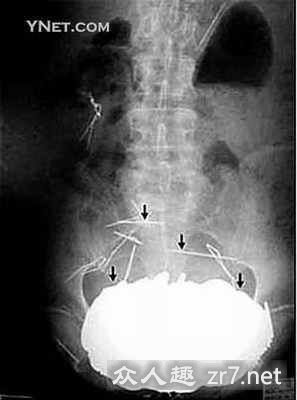

2002年,法国一名62岁的老者因胃痛难忍,不能下咽任何食物,来到法国西部的让丽特总医院急救室,当医生发现这名患者的病因后大吃一惊。在这名患者的胃里竟然发现了350枚硬币!合计650美元,同时还发现有项链和钢针等。患者家人告诉医生,老人原患有精神病,有时他吃硬币,以前也曾到过医院,从胃里取出过一些硬币。

让丽特总医院的医生们给患者做了X光检查,结果显示,在患者胃里有约12磅重的不透明物质,大小与保龄球一样,因为患者胃里的东西太重,所以致使患者的胃下垂。在这位患者住院的第5天,医生为他做了手术,取出了胃里的物体,不过术后12天,该患者因并发症而去世。据医生称,该患者吞咽的硬币各种各样,有法国硬币,也有后来发行的欧元。医生还称,该患者在到别人家后,就想偷硬币吃。